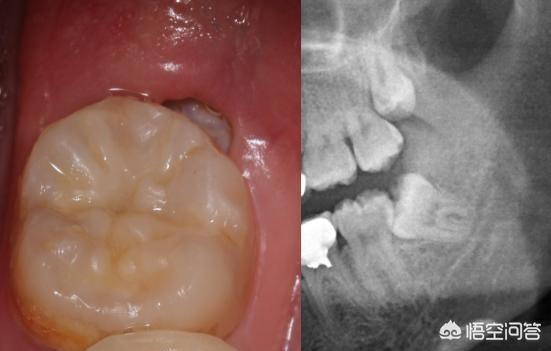

Vor einem Jahr begann mein rechter Weisheitszahn zu schmerzen, damals jedoch nur gelegentlich und in einem erträglichen Ausmaß. Nach sechs Monaten mit sporadischen Schmerzen wurden die Zahnschmerzen immer schlimmer. Als ich einmal einen scharfen Eintopf aß und ein paar Tage hintereinander wach blieb, waren die Zahnschmerzen so schlimm, dass ich nicht schlafen konnte, und ich erlebte, was es heißt, Zahnschmerzen zu haben, die einen nicht krank machen, sondern umbringen.

Am nächsten Tag war mein halbes Gesicht geschwollen, und ich musste ins Krankenhaus gehen. Nach der Untersuchung im Krankenhaus sagte der Arzt, dass meine Weisheitszähne entzündet waren und Karies auftraten, auch bekannt als Wurmzähne.

Der Arzt empfahl mir, meine Weisheitszähne ziehen zu lassen und meine Karies zu füllen. Die Füllung habe ich akzeptiert, schließlich fangen die in der Mitte an, sich zu leeren, das kann man nicht füllen. Aber ich weigerte mich, den Zahn zu ziehen, es sieht ein bisschen gruselig aus, und der Zahn ist weg.